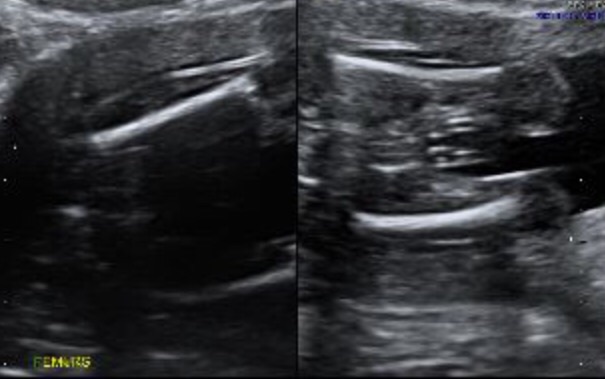

Femur shot. What's your thoughts? Boy or girl

My first thought is boy but I am not confident at all.

Thinking girl 75/25

I think girl too xx

Thinking girl

Girl